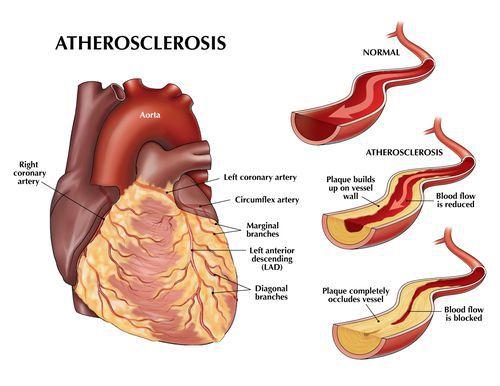

Атеросклероз – системное заболевание, при котором в первую очередь поражаются артерии. В стенке сосудов происходит отложение холестерина, вследствие чего образуются бляшки, препятствующие нормальному току крови.

Атеросклероз — системное заболевание, первоначально поражающее сосуды, но не все, а только артерии, в стенках которых накапливается холестерин и его эфиры, образующие характерные для этого заболевания бляшки. [1]

В медицине сложилась странная ситуация, когда для поражения атеросклерозом ряда органов имеются названия соответствующих «болезней», хотя фактически болезнь одна и та же: атеросклероз, и только преимущественная локализация процесса может быть разной. В частности, при наличии симптомов поражения артерий сердца (коронарных) говорят об ишемической болезни сердца (ИБС), при симптомном поражении артерий, кровоснабжающих нижние конечности — об атеросклерозе артерий нижних конечностей («перемежающаяся хромота»), а, например, при разрыве атеросклеротической бляшки и тромбозе одного из сосудов, кровоснабжающих головной мозг — об ишемическом атеротромботическом инсульте.

Атеросклероз коронарных артерий

Если атеросклеротические бляшки значительного размера ограничивают кровоток в сосудах сердца, развивается так называемая «стенокардия напряжения» — боль в грудной клетке или дискомфорт (тяжесть, жжение, сдавливание в груди) при физической нагрузке — ходьбе, беге, подъеме тяжестей.

Атеросклероз артерий нижних конечностей

Если то же самое происходит в артериях нижних конечностей, развивается симптоматика, которая получила название «перемежающаяся хромота», при которой во время ходьбы появляется боль, жжение или резкая усталость в мышцах ног. Эти симптомы довольно быстро проходят, если остановиться, но возникают через некоторое время опять при продолжении ходьбы.

Атеросклероз сосудов головного мозга

Наиболее серьёзными проявлениями атеросклероза сосудов головного мозга является ишемический инсульт и транзиторная ишемическая атака.

Атеросклероз почечной артерии

Атеросклероз почечных артерий может приводить к артериальной гипертензии, в том числе устойчивой к лечению.